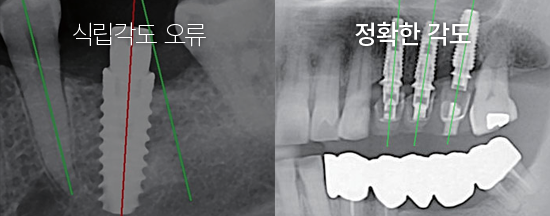

ÀÇ»çÀÇ °æÇè¿¡ ÀÇÇØ¼¸¸ ¼ö¼úÇÒ °æ¿ì, ½Ä¸³°¢µµ°¡ Ʋ¾îÁö´Â µî ÃÖÀûÀÇ À§Ä¡¿¡ ÀÓÇöõÆ®¸¦ ½Ä¸³Çϱâ Èûµç °æ¿ì°¡ ¸¹½À´Ï´Ù. ÄÄÇ»ÅÍ »ó¿¡¼ ¸ðÀǼö¼ú ÈÄ ÃÖÀûÀÇ ÀÓÇöõÆ® ½Ä¸³ À§Ä¡¸¦ °áÁ¤ ÇϹǷΠÁ¤È®ÇÏ°í ¾ÈÀüÇÏ°Ô ÀÓÇöõÆ®°¡ ½Ä¸³µË´Ï´Ù.